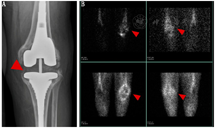

(3)假体关节感染。TPBS常被用于诊断假体关节感染,但在术后2年内骨重建过程会使其应用受到一些限制。在这一早期阶段,推荐使用WBC显像或骨髓显像,因为准确性高,具有排除诊断能力[15,33]。然而,最近1项有关慢性肩关节假体感染的研究却发现了与上述观点相悖的结果,WBC或骨髓显像的灵敏度仅为18%[37]。图2为WBC显像在1例64岁女性膝关节置换术后患者中诊断假体关节感染的示例。